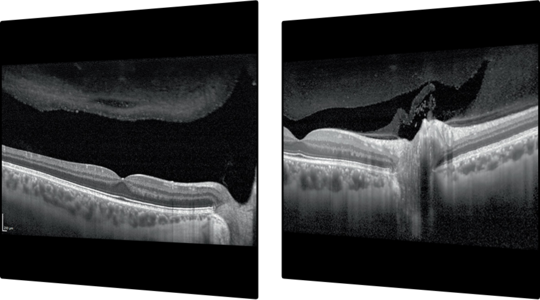

8.Módulo de Angiografia OCT

Imagem vascular não invasiva

O Módulo de Angiografia OCT SPECTRALIS® oferece imagens de OCTA de alta resolução, com uma resolução lateral de 5,7 μm/pix. Combinado com a precisão do TruTrack Active Eye Tracking, o módulo OCTA permite visualizar redes capilares finas com grande detalhe.

A resolução axial de 3,9 μm/pixel permite a segmentação de todos os quatro plexos vasculares da retina validados histologicamente. Lâminas personalizadas dentro dos plexos vasculares superficial e profundo oferecem uma avaliação clínica mais abrangente.

A ferramenta de remoção de artefatos de projeção (PAR) utiliza informações do plexo vascular superficial para remover artefatos das imagens OCTA. Isso possibilita uma visualização mais precisa da estrutura vascular e das patologias.

• Campo de visão flexível

• Remoção de Artefatos de Projeção (PAR)

• Angiografia Hibrida

• Imagem Multimodal com OCTA